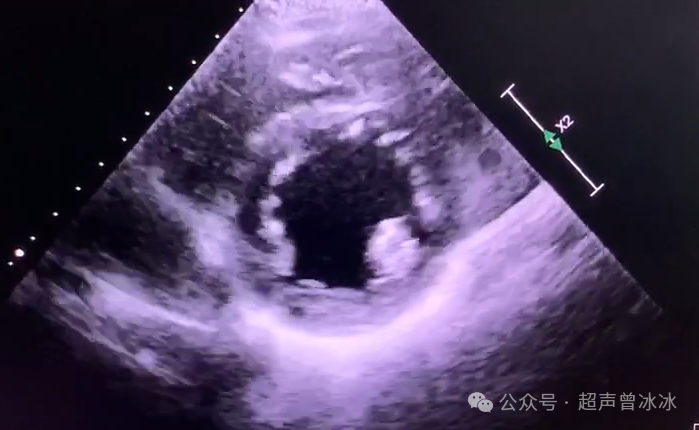

对应到超声图像就是↓

2379d9bb5cb76627c2bfa05e449e24dc3f9fd0cdb70bf77f97d7b58eed1f3ea0a5628596df3061a4